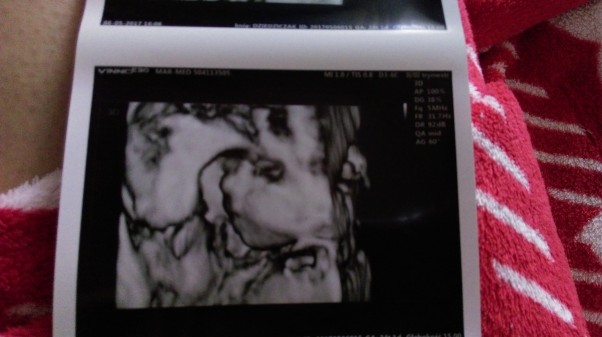

Kochani! Chciałabym się z wami podzielić spostrzeżeniami z darmowej akcij jaka miała miejsce w Centrum Handlowym Wola Park w ostatni weekend. Nie mieliśmy dotąd usg 4D dlatego bilbord reklamowy bardzo nas przyciagnął i zachęcił do udziału w akcji. Badania odbywały się w sobotę i niedzielę od 11-16. Stwierdziliśmy ze pojedziemy sobie o 10 zrobimy zakupy wcześniej i o 11 zgłosiły się na badanie. Dotarliśmy do Wola Parku o 10.20 jakie było nasze zdziwienie jak zobaczyliśmy w kolejce tłum kobiet które tak jak my chciały zobaczyć buzię swojego Maluszka.... Ale postanowiliśmy ustawić się na końcu kolejki i grzecznie czekać. Praktycznie każda Pani była z mężem lub osoba towarzysząca więc troszkę też robił się sztuczny tłum i stwierdziliśmy ze nie jest tak strasznie i damy radę :) w ciągu kilkunastu minut za nami ze zebrało się jeszcze więcej osób niż było przed nami :) o godz 11 rozpoczęły się zapisy dla każdej osoby na konkretną godzinę żeby moc zgłosić się 15 minut wcześniej i nie czekać kilku godzin na swoją kolejkę ( tu wielki plus za taki pomysł). Przychodzi w końcu ten moment kiedy podchodzimy do zapisu i ...okazuje się że miejsca na dziś na 4d już się skończyły :( jesteśmy zapisami na listę rezerwową na 4miejscu. Ale możemy skorzystać ze zwykłego usg 2d. Więc co robić korzystamy ze zwykłego na 14.30. Pojechaliśmy do domu żeby tam bez sensu nie siedzieć i wrocilismy. Chyba ktoś zrezygnował z czekania bo weszłam od razu jak przyjechaliśmy o 14.10. Pani dr która wykonywała badanie bardzo precyzyjna, myślałam że skoro jest to za darmo to będzie "byleby następna" Ale absolutnie nie. Badanie ze sprawdzeniem wszystkich narządów bardzo bardzo dokładne. Po badaniu pojawiło się światełko ze skoro jest do przodu 2d to może zalapiemy się z listy rezerwowej na 4d. Tutaj niestety (dla nas) wszystko szło zgodnie z planem. Ale przemiłe Panie powiedziały ze mozmy spróbować i zaczekać. Stwierdziliśmy ze skoro i tak straciliśmy już pół dnia a nie mamy lepszych planów to poczekamy. Planowe badania skończyły się o 16. Wszyscy zaczęli się już pakować więc myślimy no i lipa... Biorąc pod uwagę że badanie trwa u jednej pacjentki 20 minut... Ale pan Dr. który wykonywał 4d był tak przesympatyczny że stwierdził że skoro jesteśmy już po 2D to wystarczy tylko porobić zdjęcia i nas przyjął :) Dziewczyny i było warto :) to niesamowite zobaczyć tak już bardziej realnie ta małą istotke która rośnie w środku nas. Także dzień zakończył się dla nas bardzo szczęśliwie. Żal mi tylko tych Pań którym się nie udało :( cała obsługa akcji była przemiła Ale na przyszłość powinni lepiej zorganizować możliwość uczestniczenia w takiej akcji bo chyba żadna kobieta z brzuszkiem nie chce lecieć i stać 3 godziny wcześniej w kolejce. Pozdrawiam wszystkie Mamusie :)